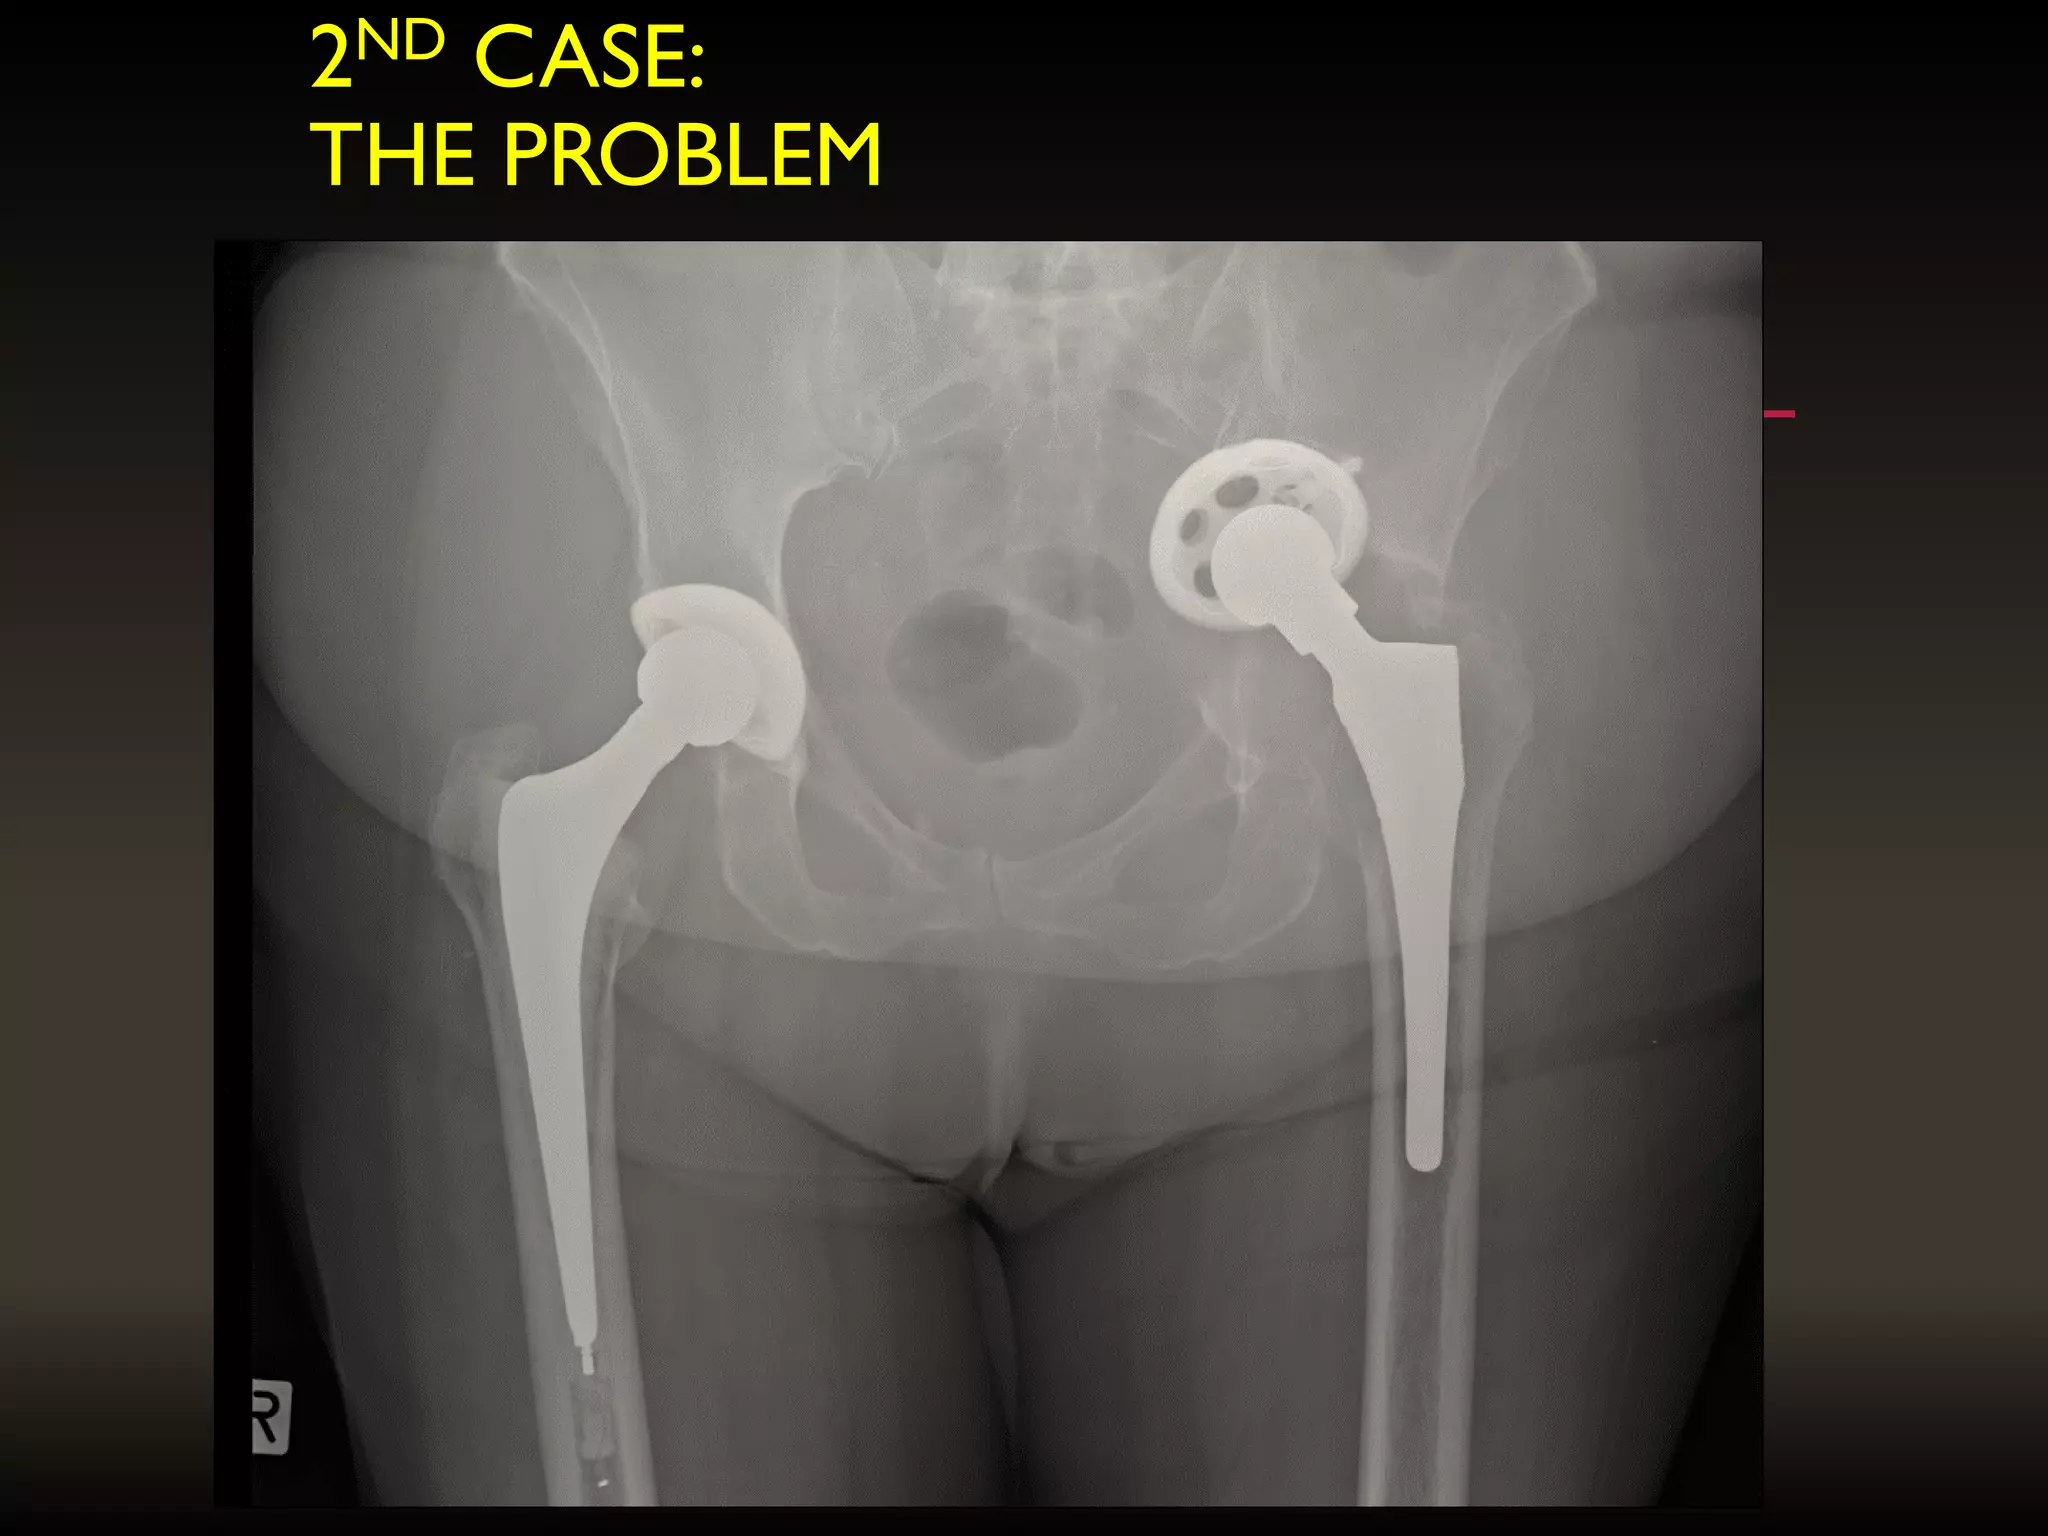

2ND CASE:

THE PROBLEM

THE BIO-MODEL OF THE PELVIC DISSOCIATION AND IIIB

OUTLINE OF THE PROPOSED IMPLANT

Fracture line

through

posterior column

= 2 parts

• 8.

• 9.

THE BIO-MODEL OFTHE PELVIC DISSOCIATION AND IIIB OUTLINE OF THE PROPOSED IMPLANT Fracture line through posterior column = 2 parts THE NEED FOR CUSTOM IMPLANTS (HIP)